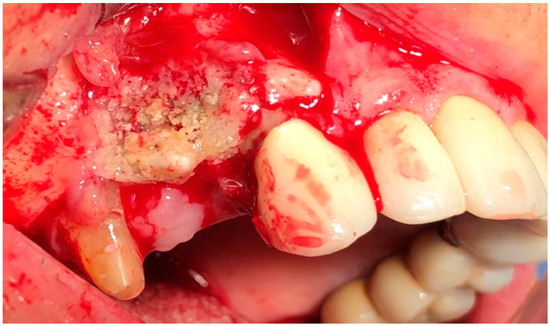

Management of Medication-Related Osteonecrosis of the Jaw (MRONJ) Using Leukocyte- and Platelet-Rich Fibrin (L-PRF) and Photobiomodulation: A Retrospective Study